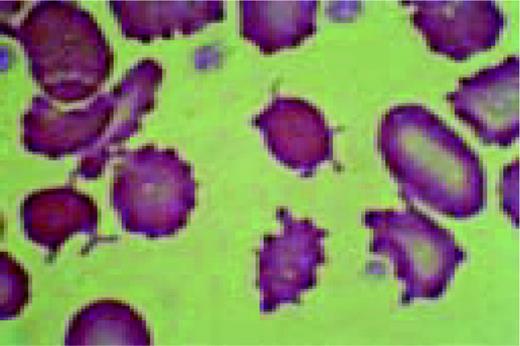

Bernard-Soulier syndrome. High-oil magnification view of a patient with the Bernard-Soulier syndrome. A typical giant platelet is seen in the center of the field.FIG87

Slide MG6